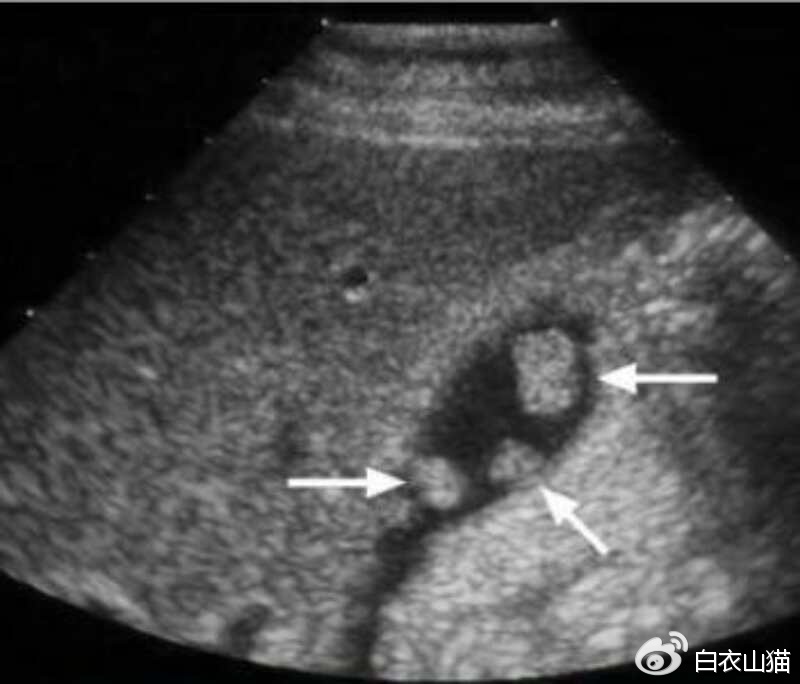

胆囊息肉的最重要检查,也是首选的检查:腹部B超。B超对人无害,又便宜。

箭头所指就是胆囊息肉

B超检查中最重要的依据是息肉大小。